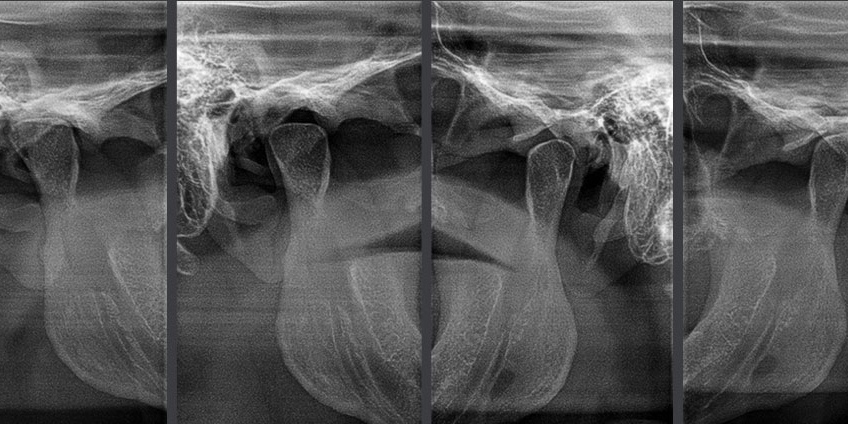

Scan & view in less than 10 seconds

Fast scan mode

4.9s

Scan

4.0s

Reconstruction

1.0s

Save